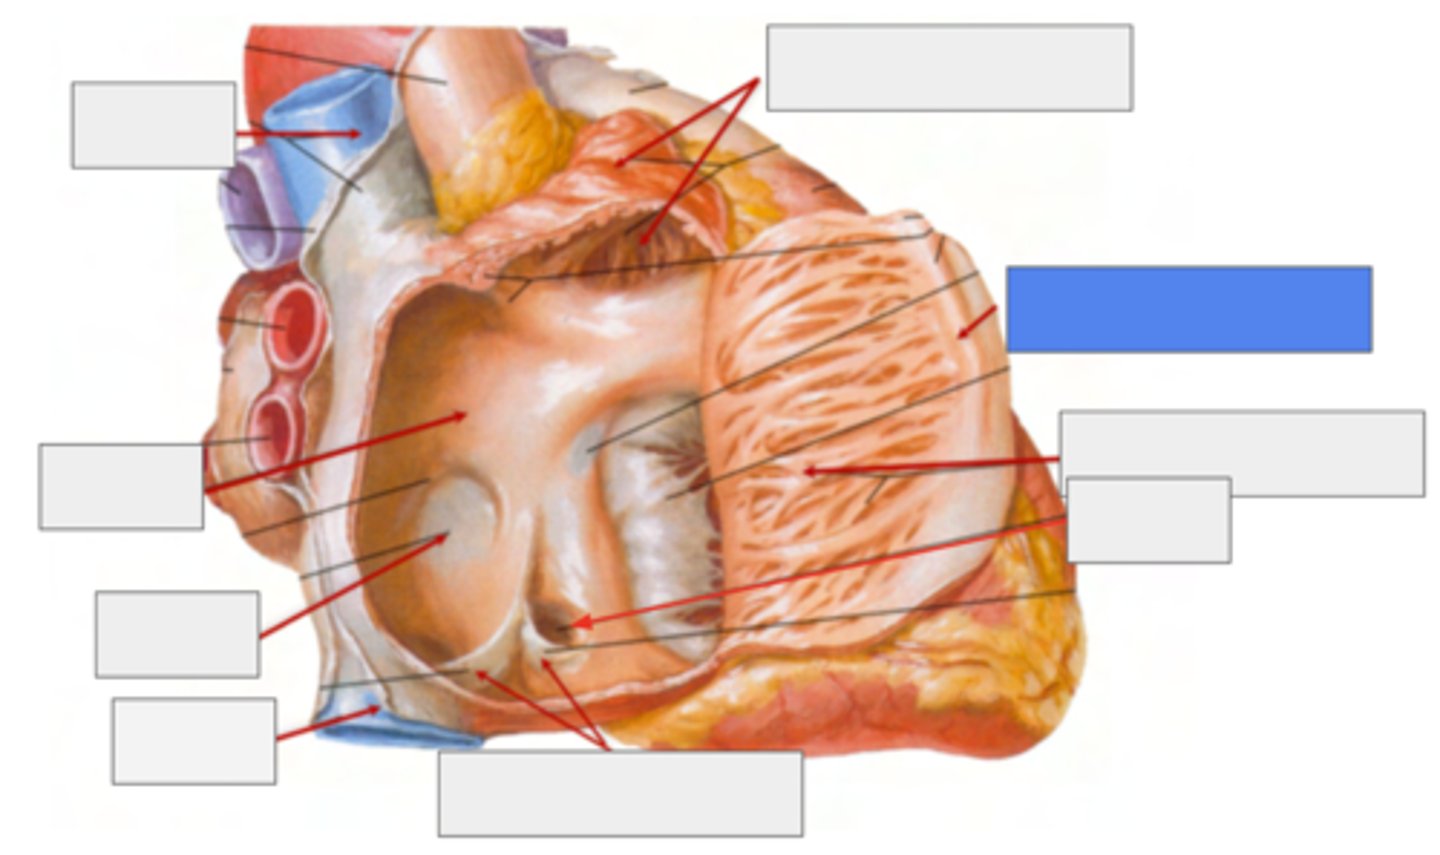

What is pointing the blue square?

valves of inferior vena cava and coronary sinus